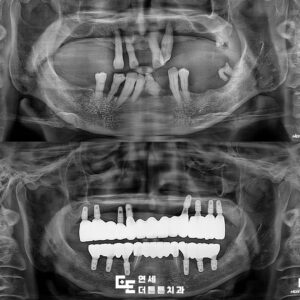

먼저, 처음 내원 당시 채득한

환자분의 바이트를 참고하여

진단 모델을 제작한 후

CT 촬영을 통해 가상 모의 수술을

진행하여 수술용 스텐트를 제작하였습니다.

수술 후 4개월 뒤 최종 인상을 채득하였고

환자분의 구치부 교합 안정성을 위해

임시치아를 제작하여 4주간 사용하실 수

있도록 하였습니다.

4주간의 임시치아 사용 후

맞춤형 지대주를 연결하여

최종 지르코니아 크라운을 장착하고

교합 조정을 시행하여 주었습니다.